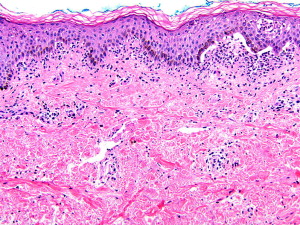

CBDC is diagnosed by hematoxylin-eosin–stained biopsy and immunofluorescence testing. Histology is characterized by a subepidermal blister with a primarily neutrophilic infiltrate in the papillary dermis, although mononuclear cells and occasional eosinophils are also seen ( Fig. 3 ). Immunofluorescence testing of perilesional skin is the gold standard for diagnosis and shows linear IgA staining along the BMZ ( Fig. 4 ). For unclear reasons, the volar forearm seems to be an inferior site for biopsy because immunofluorescence testing may give a negative result. Circulating autoantibodies are of the IgA1 subclass and can be found in more than 90% of patients. Autoantibodies bind the epidermal side of salt-split skin in most patients; however, antibody binding to the dermal side of salt-split skin or to both the epidermal and dermal sides occurs in some. The heterogeneous indirect immunofluorescence pattern is explained by the variety of antigenic epitopes, as described later. The lesions are sterile unless they have become secondarily colonized or superinfected with bacteria.